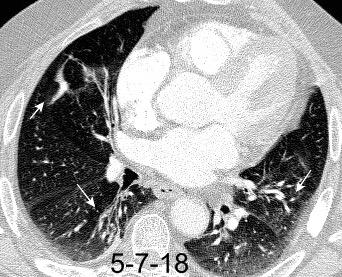

Linfoma de Hodgkin escleroso-nodular

Mediastinitis fibrosa. Fibrosis retroperitoneal.

10-20% de los casos de FM difusa

Reacción a Enf. Autoinmunes. (LED, AR)

Hematopoyesis extramedular

Metersigida / Radioterapia. Enf. inmunoglobulina IgG4. (Riedel, Colangitis, etc.)